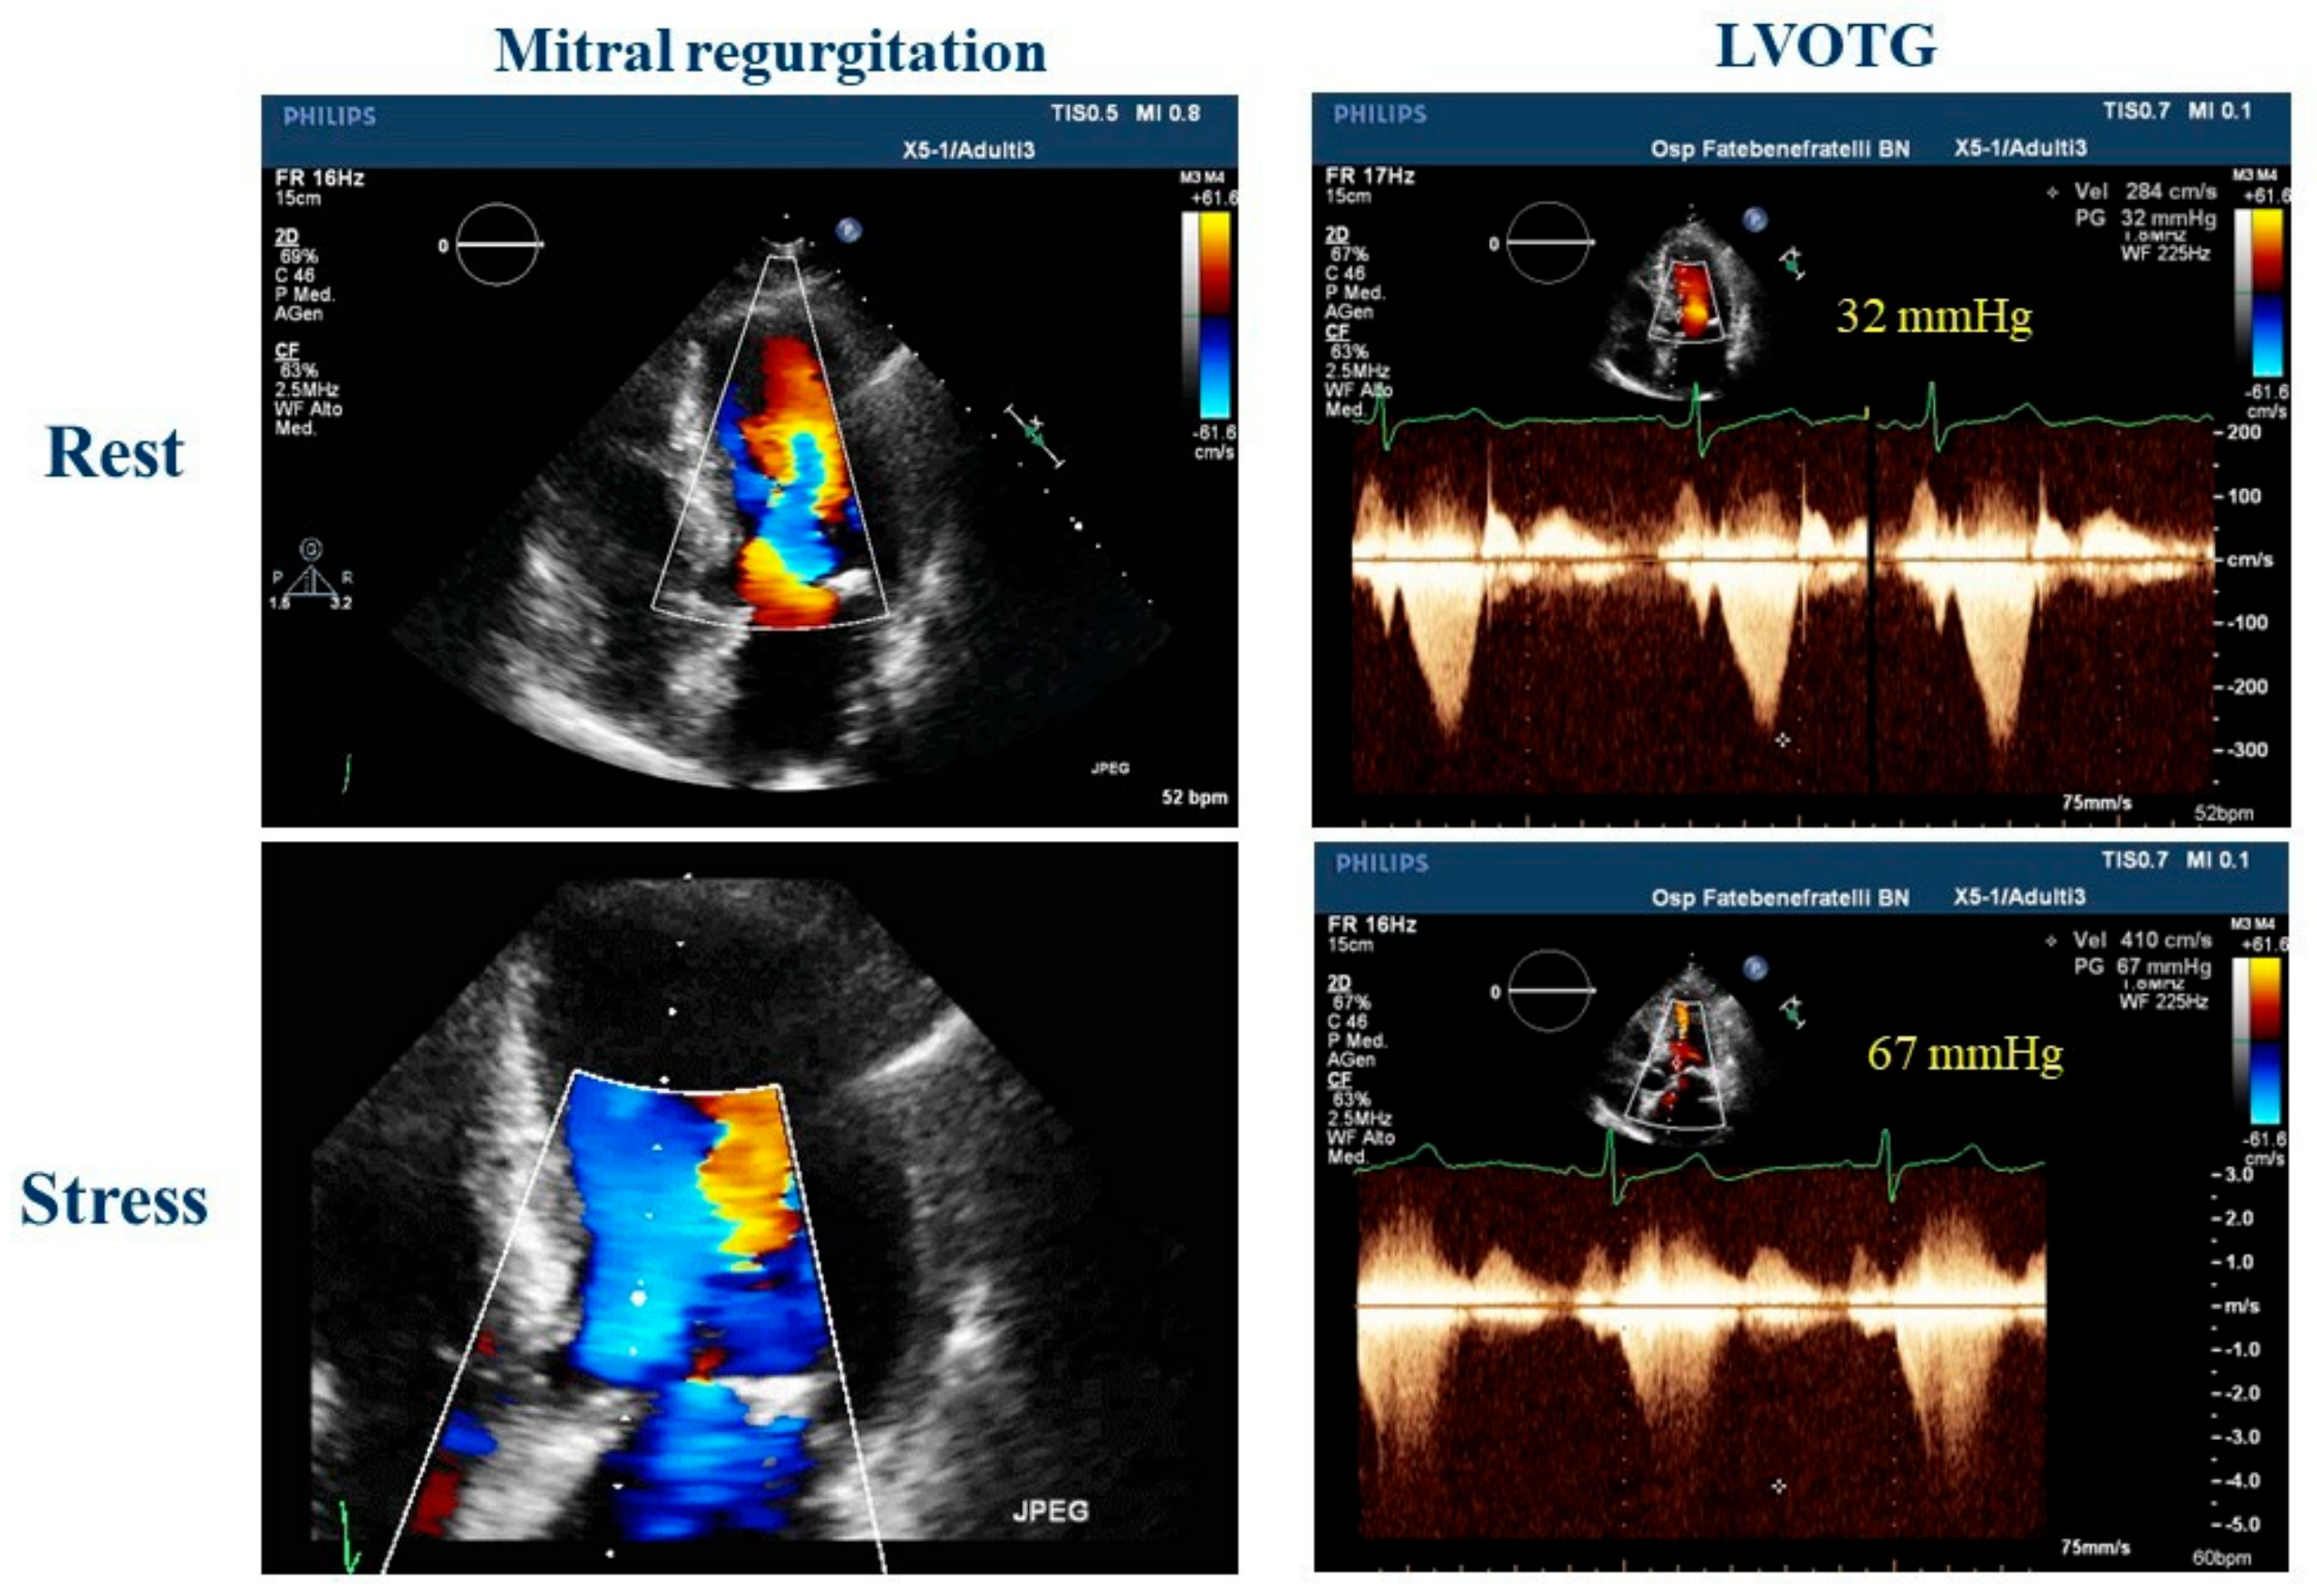

2.4. Valvular Heart Disease

| Heart valve diseases | Absent | Dynamic/functional new onset/worsening valve diseases |